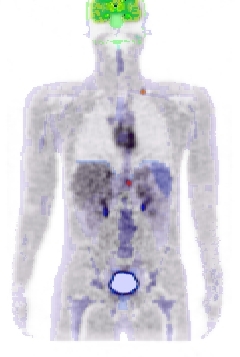

Figure 2. left: coronal slice through the Zubal phantom with inserted lesions (red points). Middle: simulated PET image corresponding to the Zubal model. Right: superimposed label model and PET simulated data.